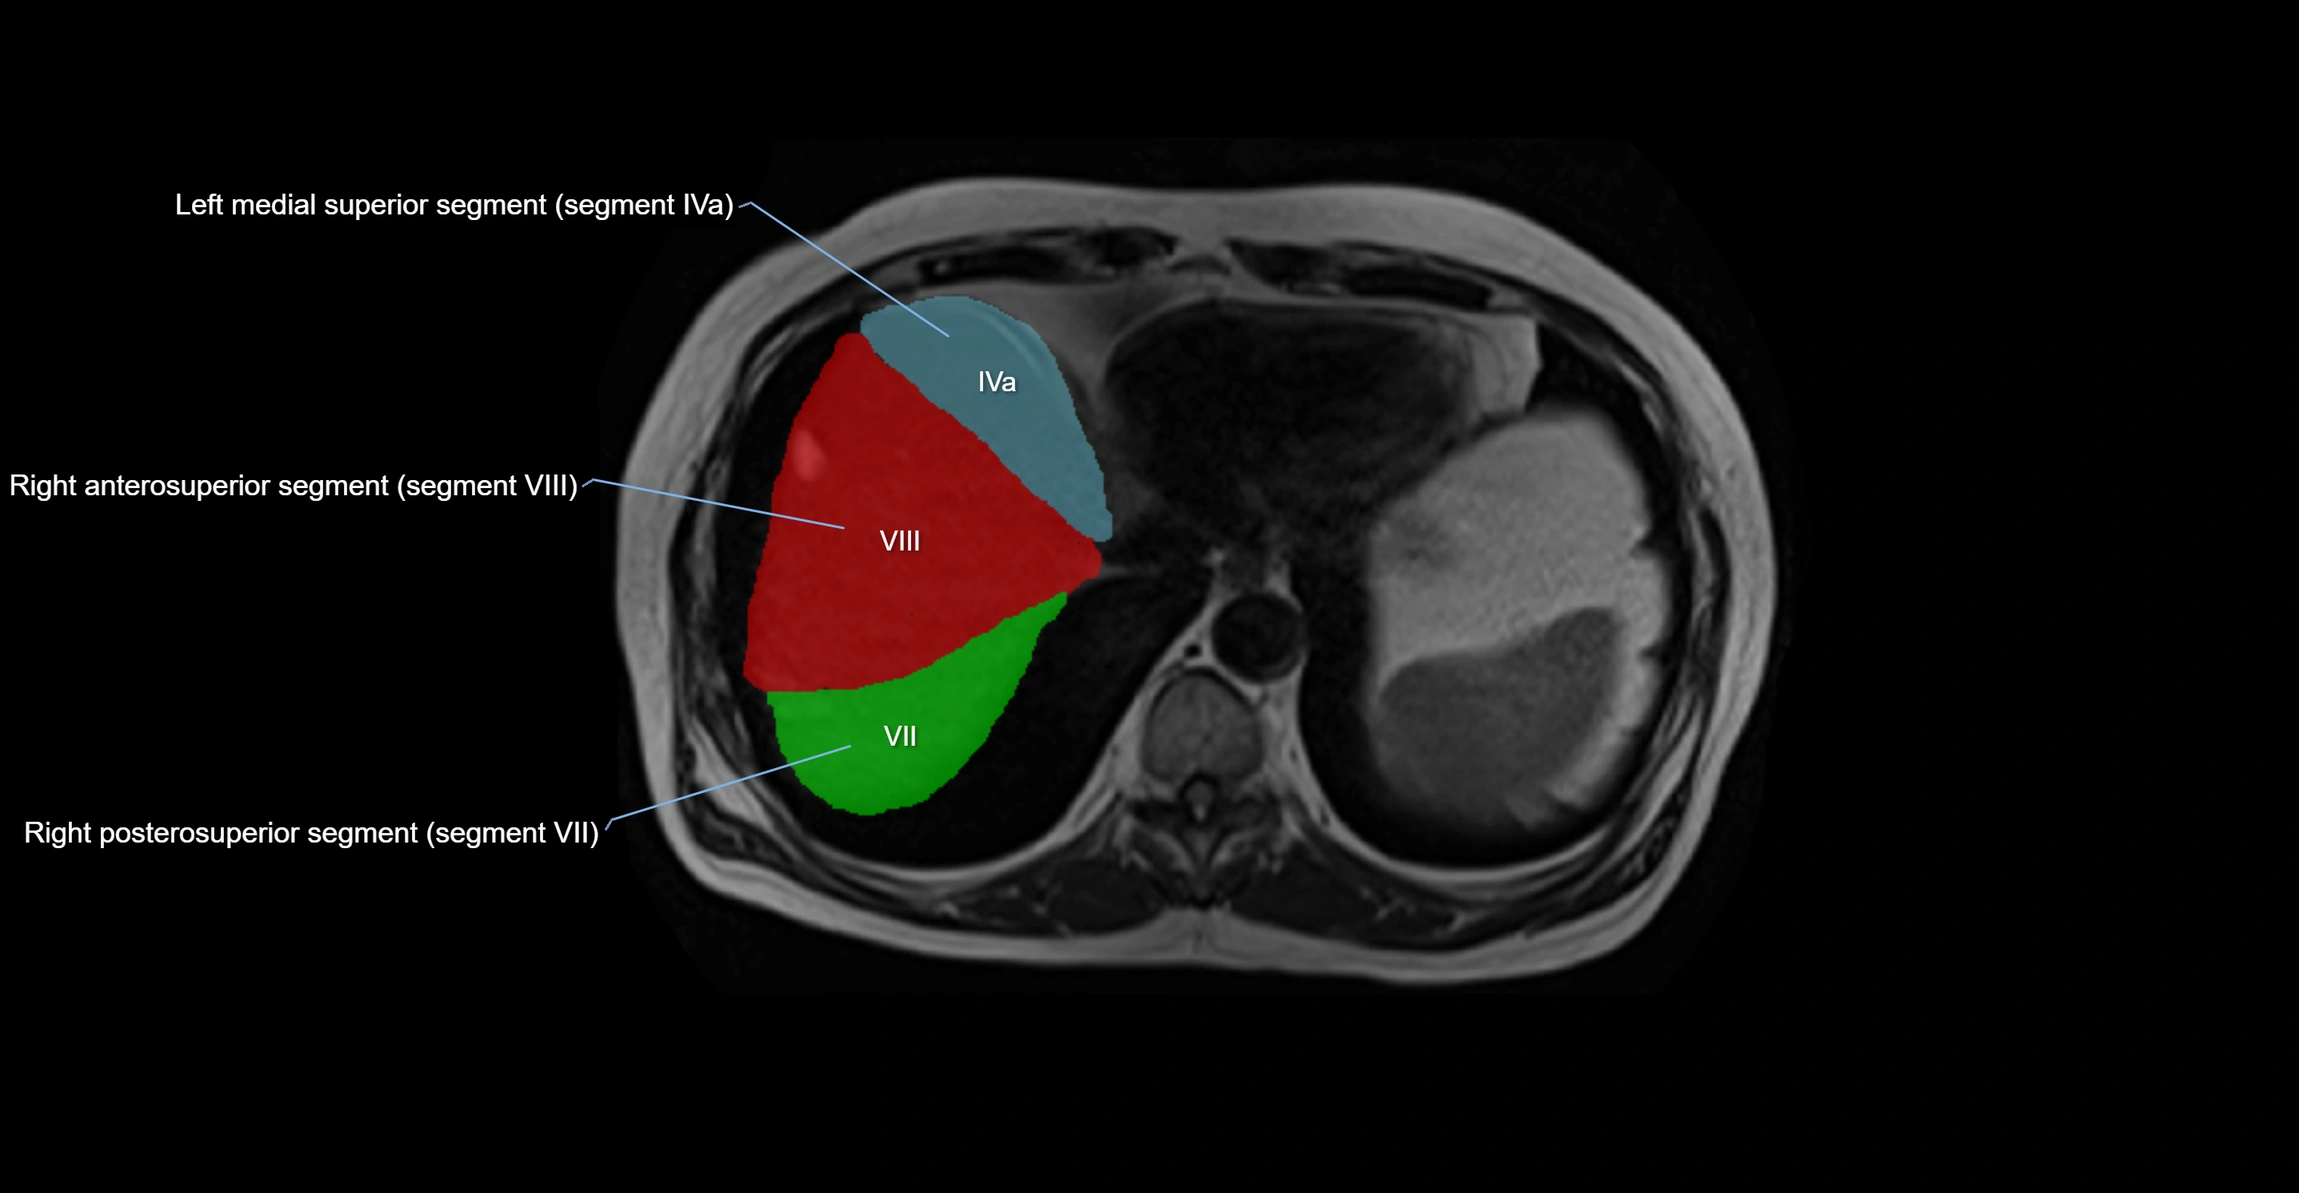

MRI image

image